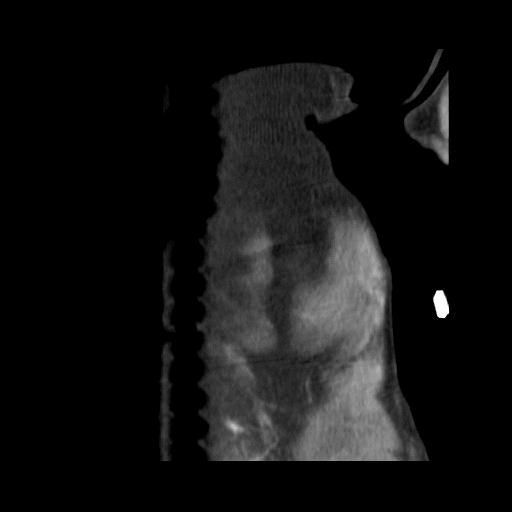

엑스레이 사진과 CT 사진(흉부 앞, 우측 옆)은 첨부하였습니다.

폐 우측 위쪽에 원발성 암이 발생한 것으로 보였습니다.

식도와 심장을 눌러서 기침을 발생시켰습니다.

나쁜 소식은 심장과 혈관이 위치한 안 좋은 부위에 암이 있다는 것이고,

좋은 소식은 심장과 혈관과 아직 붙지 않고 떨어져 있다는 것이었습니다.